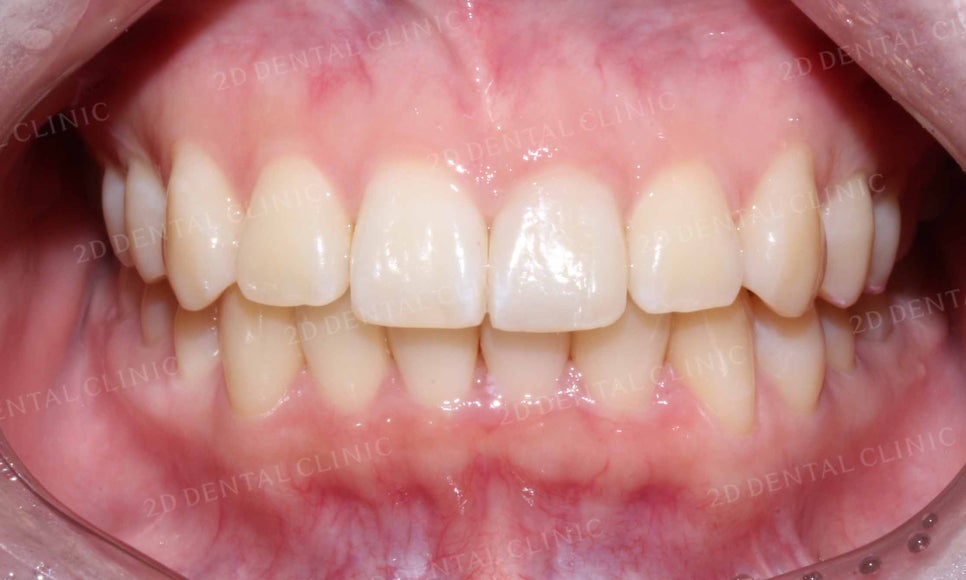

삐뚤삐뚤한 치열이었던 아랫니 역시

토끼앞니 교정 후 치열의 총생이 사라지고

완만한 곡선의 형태로 교정된 모습입니다.

이번 환자분께서는

토끼앞니 증상을 교정하기 위해

약 7개월의 교정 기간이 소요되셨으며

교정기간 중 심미성을 고려하여

2D교정방식을 선택하셨습니다.